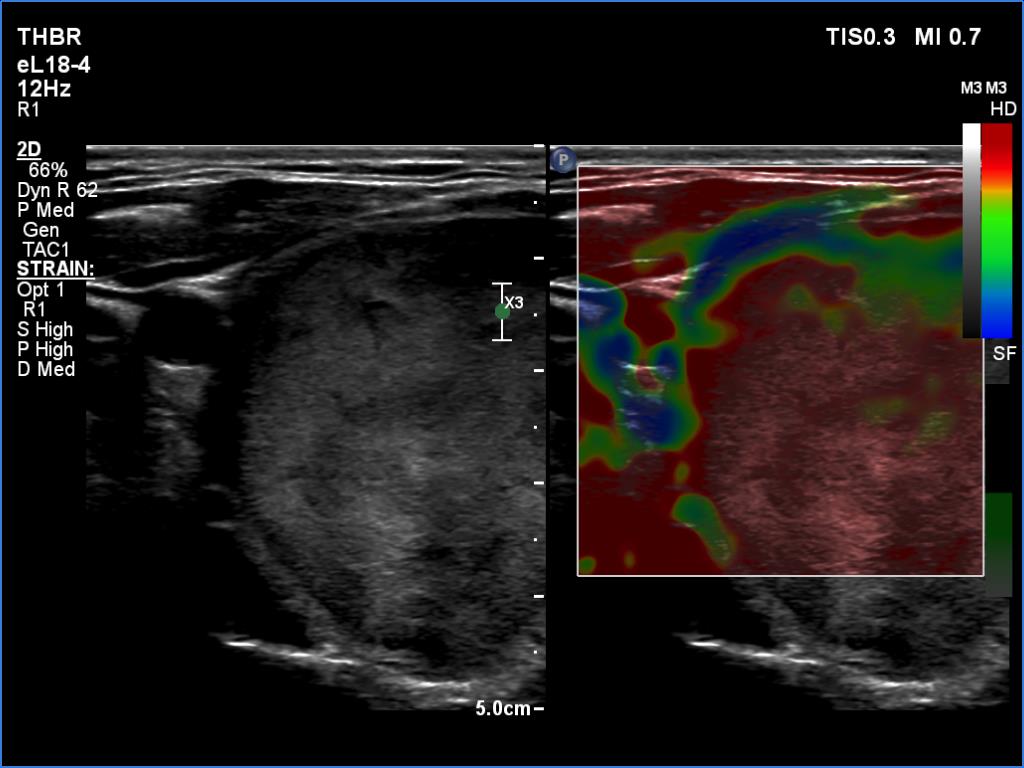

The operated thyroid - case 1641 (ultrasonographic picture 7)

Right lobe, transverse view, elastography. The nodule proved to be hard.